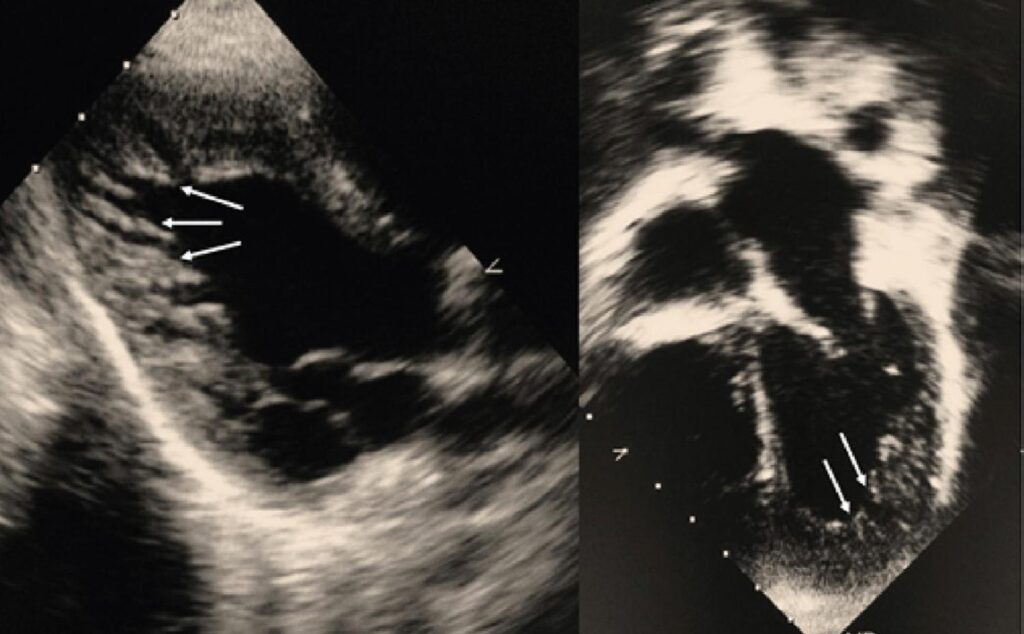

Miocardiopatia não compactada (MCNC) caracteriza-se por hipertrabeculações e recessos profundos no ventrículo esquerdo, com apresentação clínica heterogênea, desde pacientes assintomáticos a insuficiência cardíaca (IC), eventos tromboembólicos arritmias com risco de morte súbita. Por ser rara e não apresentar critérios diagnósticos bem definidos, sua história natural na pediatria é pouco conhecida. Este estudo descreve a apresentação e evolução clínica de pacientes portadores de MCNC.

Analisados seis pacientes com MCNC, de 4 a 14 anos de idade, média de idade de 7,5 anos (DP: 3,93), 3 do sexo masculino (50%). Apresentando-se com IC (n=2), sopro cardíaco (n=1), arritmia cardíaca (n=1), assintomático (n=1) ou em investigação de síndrome genética (n=1). Fenótipos ao ECO: MCNC/Miocardiopatia dilatada (n=1) e MCNC/Miocardiopatia restritiva (n=1), fenótipo isolado de MCNC (n=4). A ressonância magnética cardíaca foi realizada, confirmando o diagnóstico (n=4). Os desfechos observados foram tromboembolismo, indicação de transplante cardíaco e taquicardia ventricular sustentada.